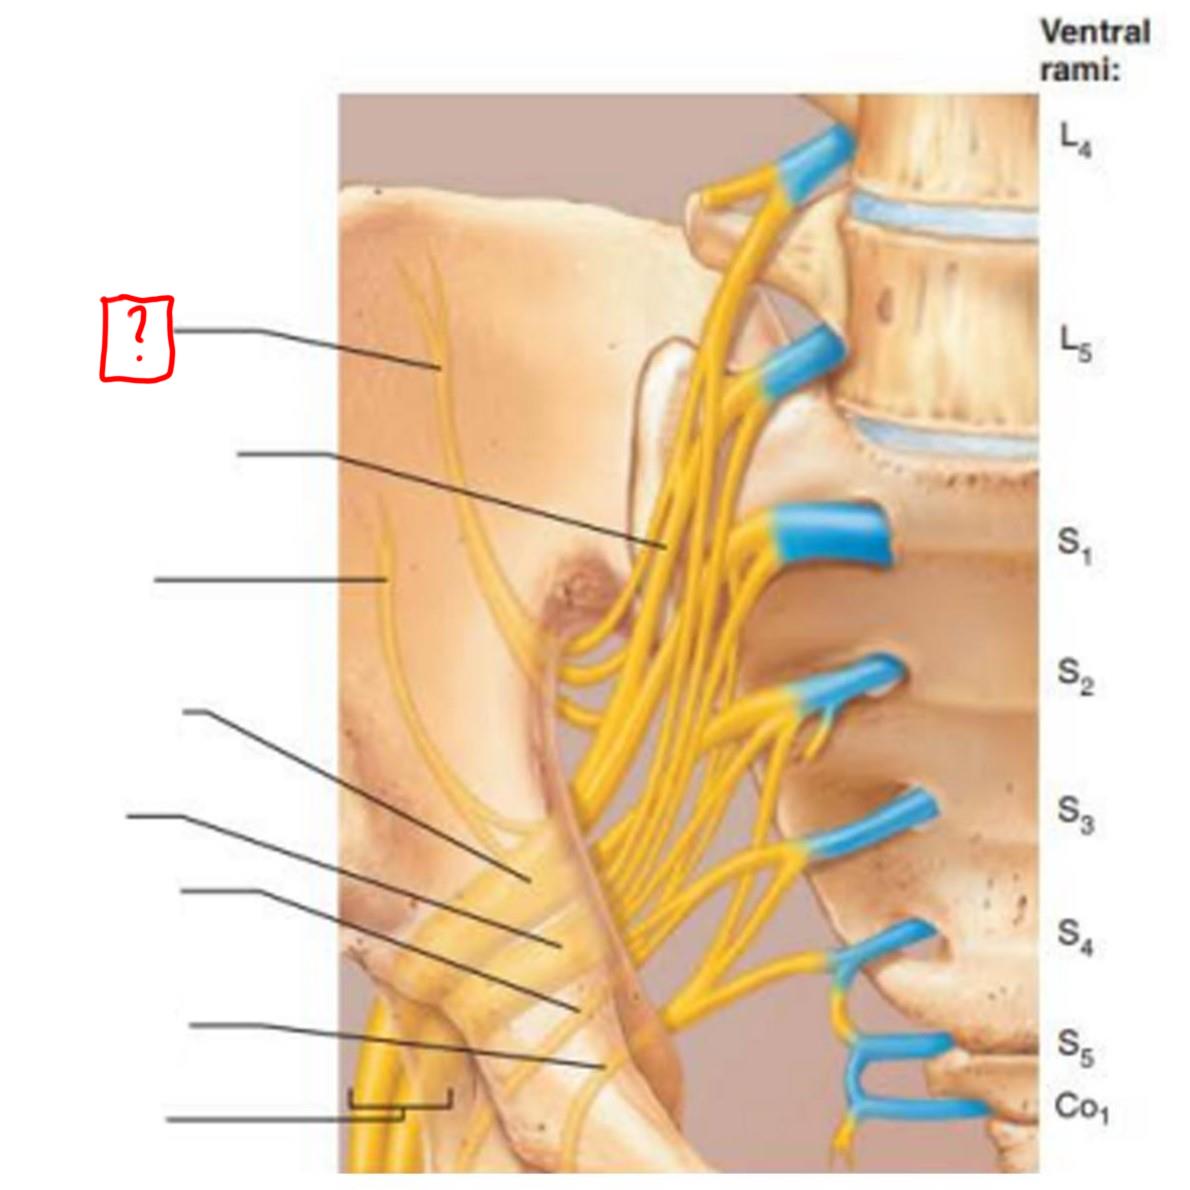

sacral plexus

L5-S4

superior gluteal

inferior gluteal

pudendal

sciatic

posterior femoral cutaneous

superior gluteal

lumbosacral trunk

inferior gluteal

common fibular

tibial

posterior femoral cutaneous